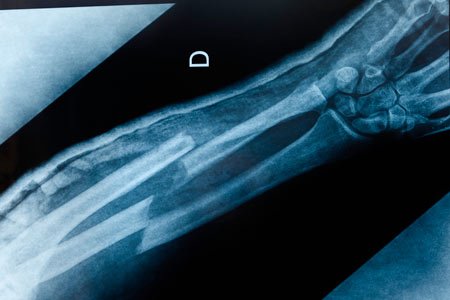

Orthopedic Care for Broken Bones and Trauma at Henry Ford Hospital

Broken bones, fractures and dislocations are common injuries. But they also demand quick, expert care in order to heal correctly. The members of the broken bones and trauma team at Henry Ford Health are leaders in the field. We provide expert care for even the most complex broken bones and orthopedic trauma.

Henry Ford Hospital, our Level I trauma center, features a dedicated orthopedic trauma operating room for complex injuries. Our multispecialty team of musculoskeletal traumatologists, trauma-trained physician assistants and nurse practitioners works together to quickly treat even the most serious traumas.